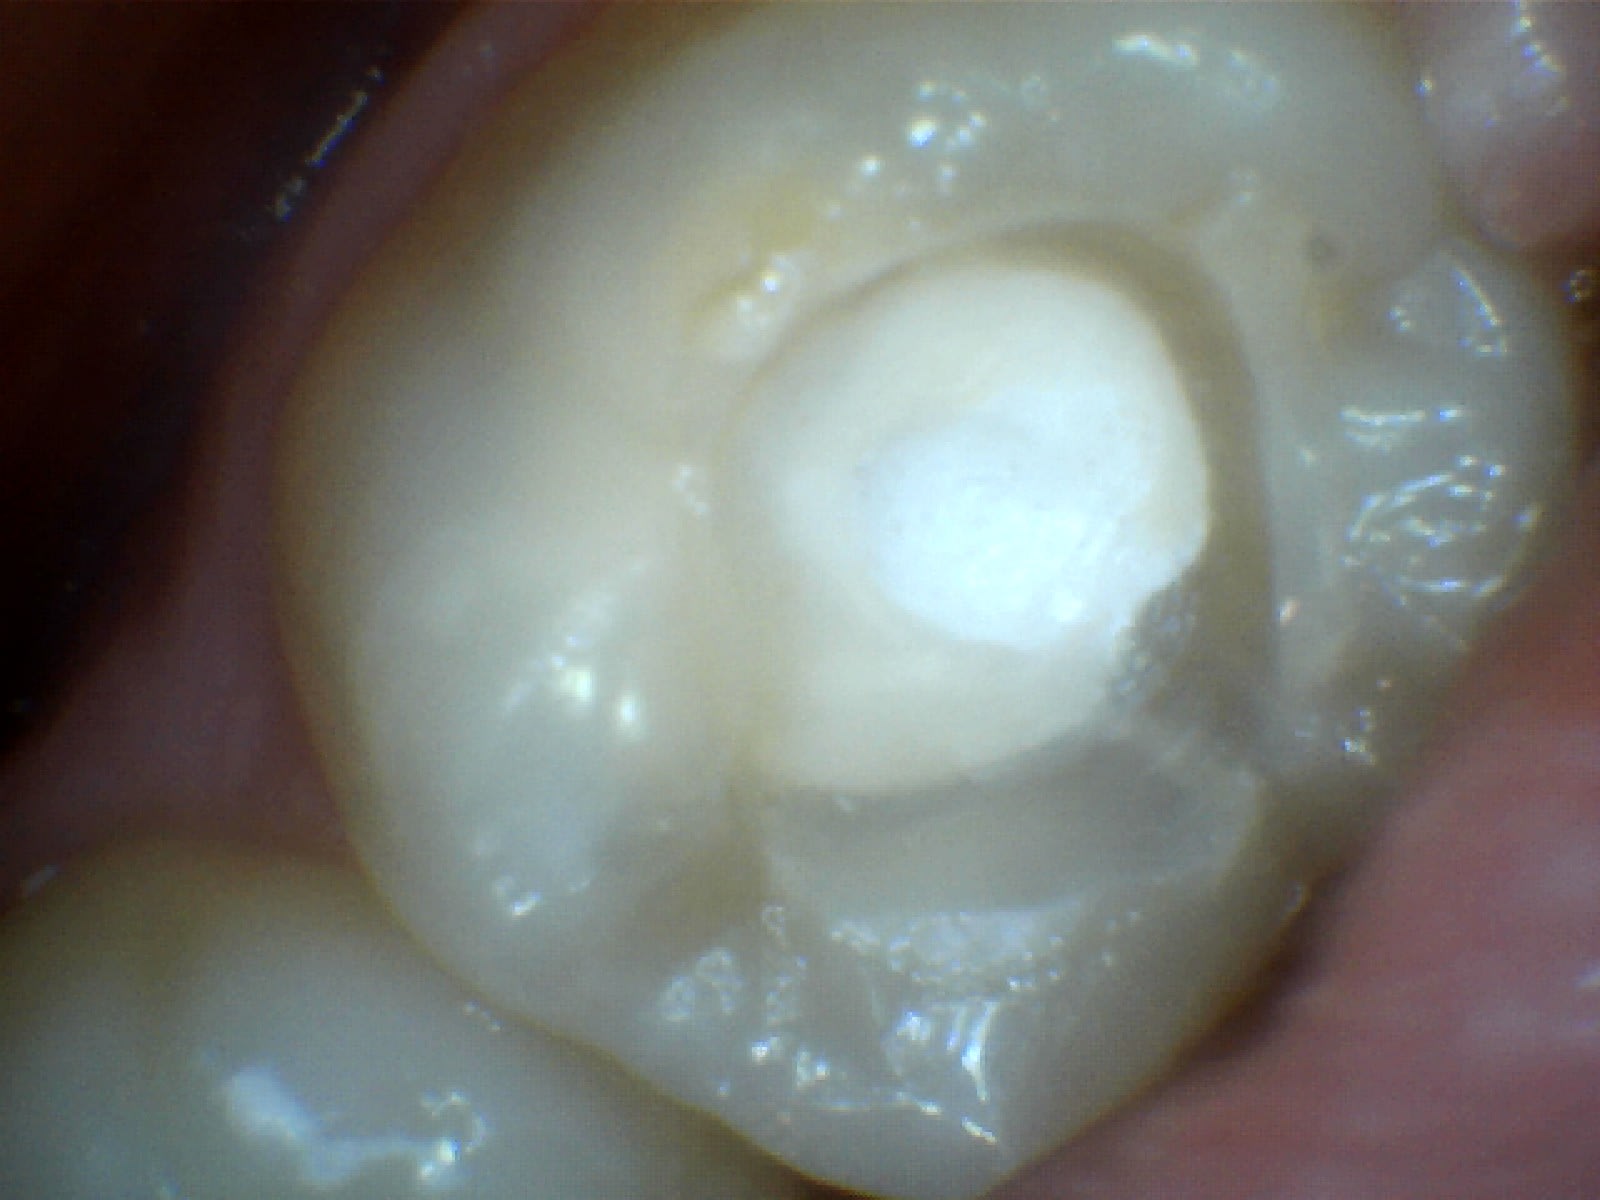

du coup j'ai revu le patient

j'ai démonté le soin, j'ai vu le fond de cavité que j'ai deposé mais pas de carie dessous visible

j'ai remis de la résine sans fond de cavité,

J'ai prévenu le patient des risques de sensibilité post op qui pouvaient venir à cause de fait que j'ai déposé le fond de cavité. Et que s'il y avait des sensibilités, il faudrait dévitaliser la dent.

Perso j aurais jamais pensé voir un truc aussi propre... j' avais vraiment tort. Désolé...

Je pensais trouver une dentine noire ébène... Ramollie mais assez dure... De la carie a progression très lente.

Du coup c'était quoi le fond de cav ?? Ça sentait l eugenol ??